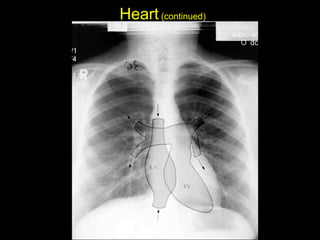

The document discusses the anatomy of the chest x-ray and CT scan by describing the lobes of the lungs and their locations. It also mentions the heart, mediastinum, hilum, and ribs. Several axial, coronal, and sagittal CT images are included with labels pointing out structures like the trachea, bronchi, lobes of the lungs, and fissures. In summary, the document provides an overview of lung and chest anatomy as seen on x-rays and CT scans through text descriptions and labeled medical images.